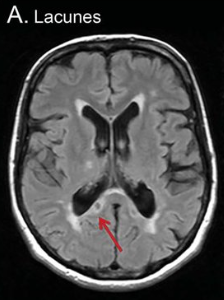

Visualizing SVD with a brain scan

Not everything can be visualized with a brain scan. For example, the small blood vessels are not visible on a scan, but the brain damage in the form of microbleeds in the cerebrum or abnormalities in the white matter are. These are called 'white matter hyperintensities'. 'Lacunar (very small) infarctions and other subcortical infarctions (under the cerebral cortex) can also be visible. Furthermore, the spaces between the walls of blood vessels and the white matter of the brain can be visible; these are the 'perivascular spaces'. C-reactive protein (CRP) can be elevated in the blood. This is a non-specific indication of inflammation somewhere in the body. CRP is predictive of SVD and is elevated when the condition is really obvious.

It was shown that people with moderate or severe white matter hyperdensity (WMH) had a high chance of increasing their SVD, while participants with mild SVD showed a mild increase over a period of 9 years. In 3.6% of the study participants, the lacunae disappeared and in 5.7% of the participants, the microbleeds disappeared, but the white matter hyperdensities could increase.

See the images of the study od Radboud University Nijmegen